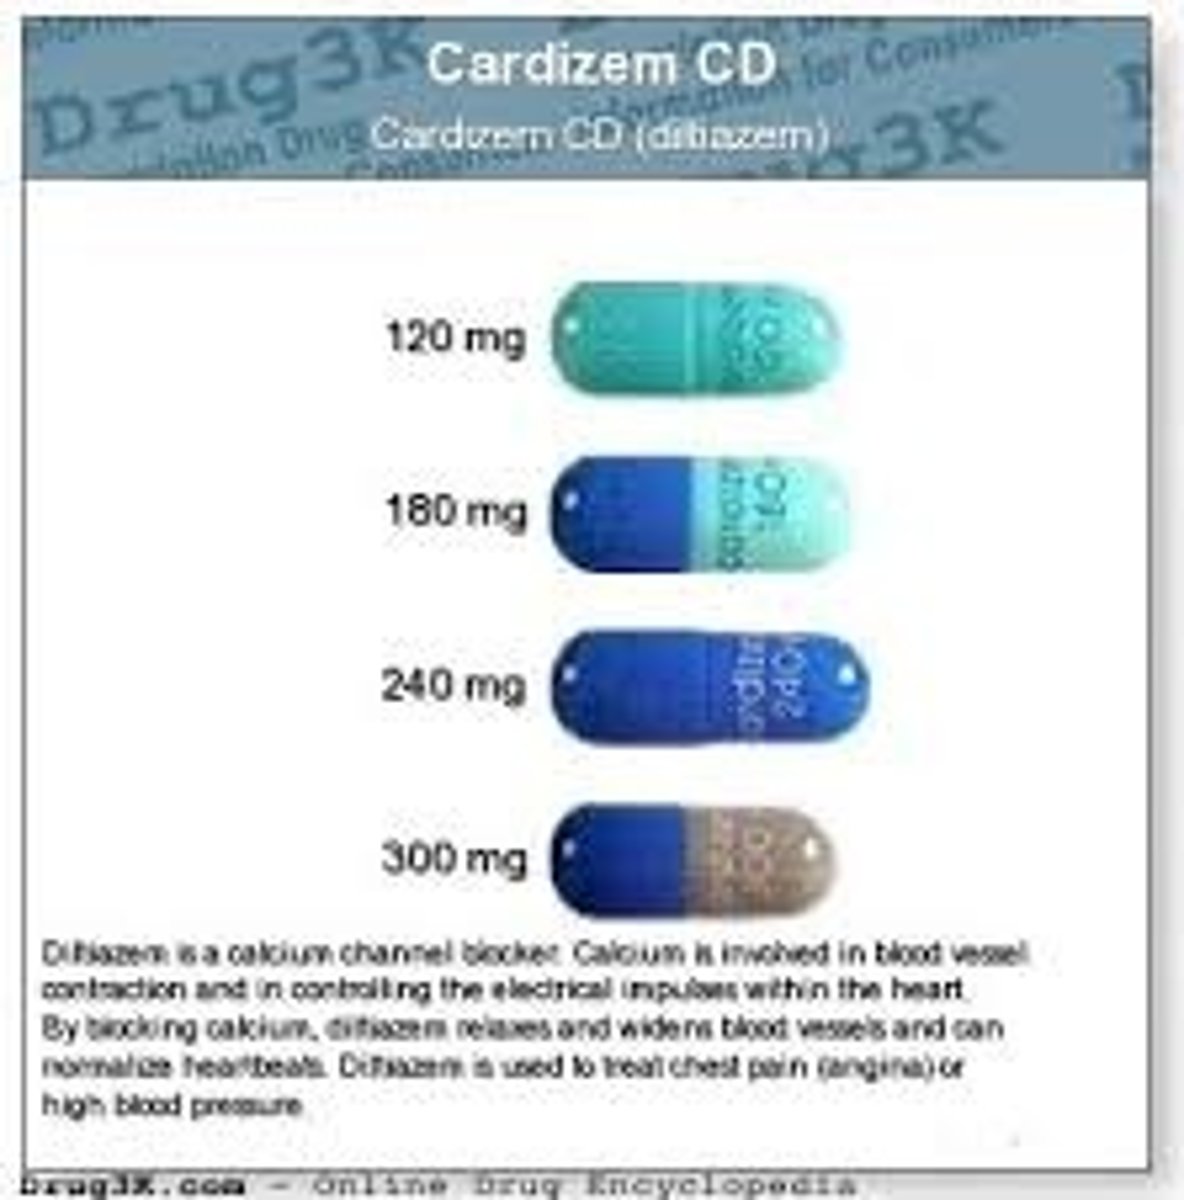

Diltiazem

Brand: Cardizem

Class: Calcium Channel Blocker

Indication: Antihypertensive

Schedule: NCLM